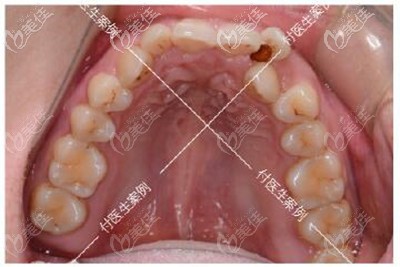

牙齿诊断:牙齿拥挤不齐+深覆合+单颗反颌+下颌方形牙弓

牙齿矫正方案:拔牙2颗、佩戴3m金属自锁托槽

拍片子、取模型、商量方案,因为我本身没有什么需求,只是希望牙齿能排齐、微笑起来不再露牙龈,而且还矫正周期短一些。

具体的治疗过程是,因为本身的牙齿问题不大,所以我戴上牙套后没几个月牙齿就排齐了,差不多一年多的时间都是在调整咬合吧,牙齿矫正过程真的酸爽,这里安利一个小技巧,在牙齿矫正期间一定要好好刷牙,要不容易黑三角,而且做好牙齿清洁后,会发现比以前刷牙干净好多。